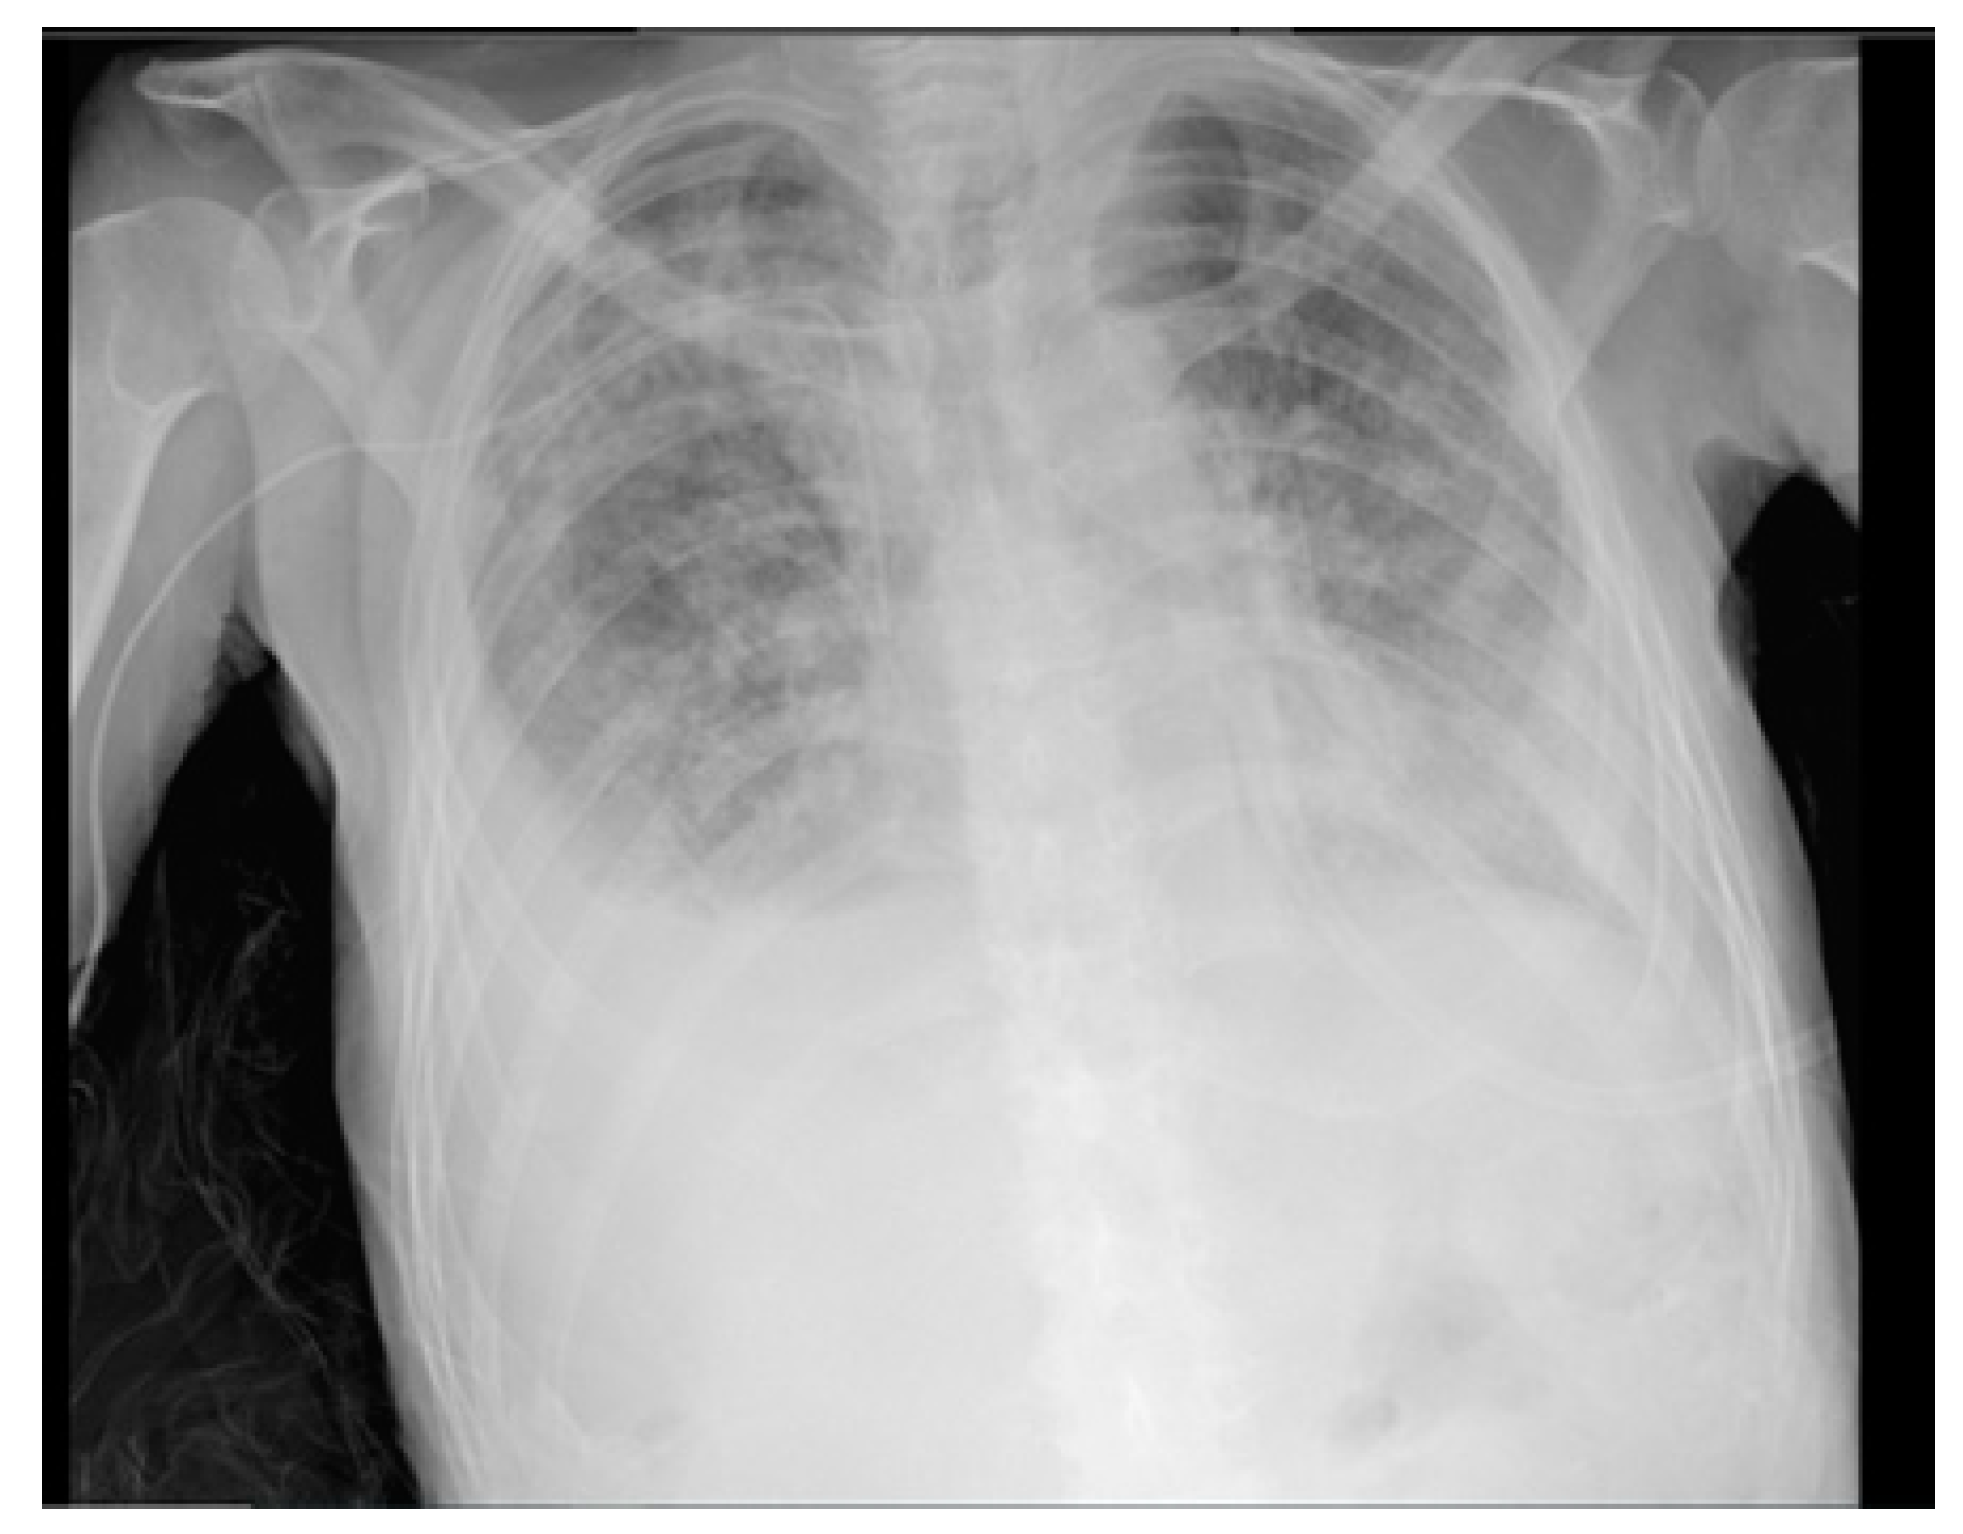

2. Case Report